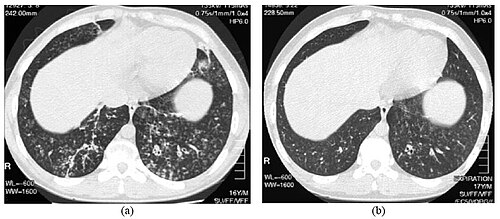

CT Thorax — Lung Window (-700 HU)

Axial CT of thorax displayed at -700 HU window level, optimized for lung parenchyma evaluation

CT Downloaded 2026-03-15

Ct

Lung Window 120 kVp W:1500 L:-700

Wikimedia Commons: CT Scan Thorax Lung -700 HU Window Level.jpg